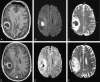

Fig 2.

Patient 1. Additional images. A–C, Follow-up images obtained 9 days later (2 weeks after drainage) show further decrease in the size of the abscess (A), persistence of low signal intensity on DW imaging (B), and a high ADC (C). D-F, Last DW images (E) (1 month after drainage) show no enhancement and no abnormality.